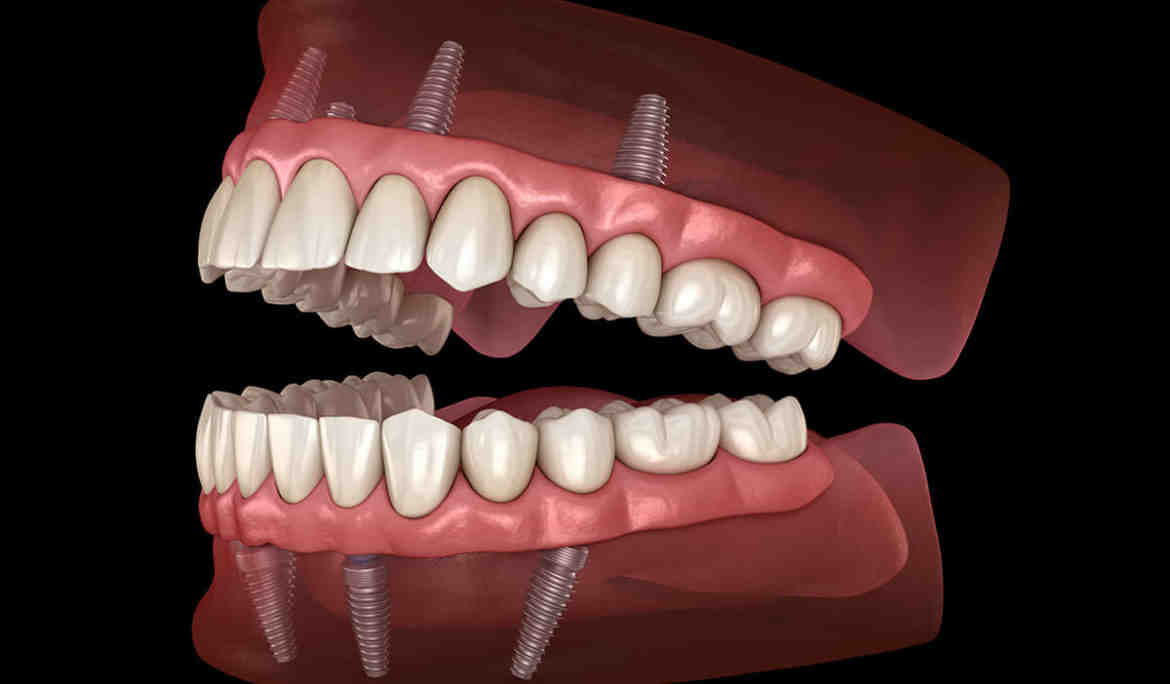

What do all on 4 implants feel like?

All-in-four dental implants are designed to be comfortable, as they do not press on the gums as traditional dentures would. You will soon be able to bite harder and experience the normal sensation of enjoying hot and cold foods and all their flavors.